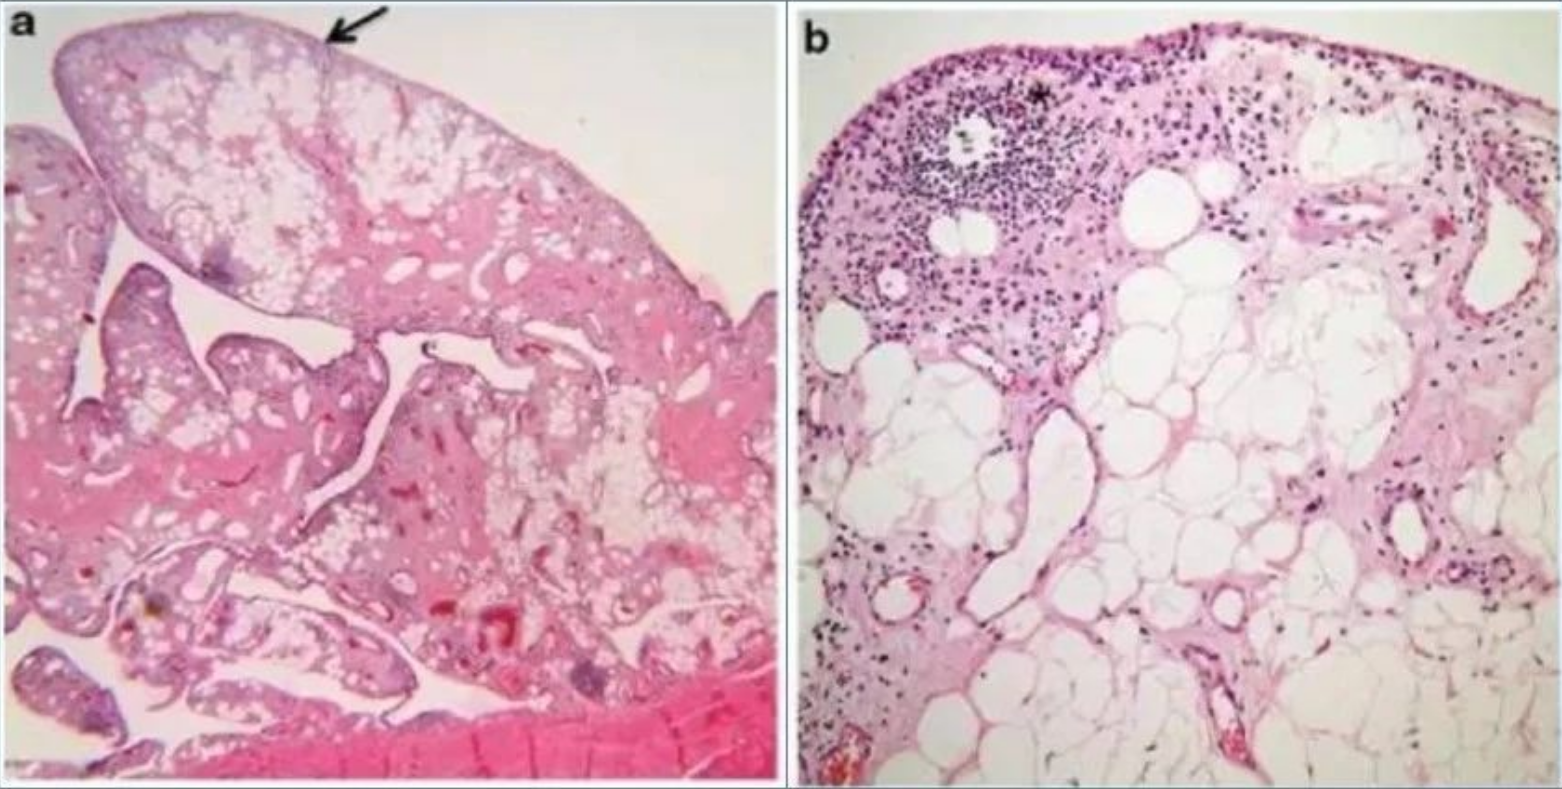

镜下观:滑膜呈绒毛状增生,滑膜下层见大量脂肪细胞浸润以及扩张毛细血管。部分病例有不同程度淋巴细胞、浆细胞浸润。